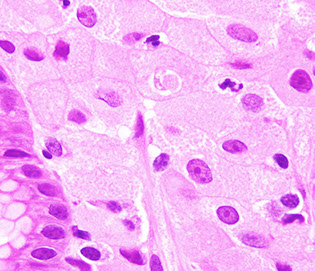

Clostridium ventriculi

Previously known as Sarcina ventriculi

- may be associated with gastric outlet obstruction such as in patients with diabetes

• Gram positive, anaerobic, sugar fermenting bacterium, S. ventriculi was first observed in the human stomach in 1842 by Goodsir . Readily found in soil and is known to cause a similar type of gastric injury in animals.

• Delayed gastric emptying and carbohydrate stasis in association with acidic gastric juices may provide an ideal culture medium

• Studied patients all had underlying delayed gastric emptying (one

had a bezoar) from diabetic neuropathy, narcotic use, and pyloric

stenosis secondary to malignancy

• The organism may simply colonize pre existing lesions but there

are too few cases to draw firm conclusions as to whether the

organism is truly a pathogen.

• Packets of 4, 8 or more cells with characteristic flattening

Clostridium ventriculi - assoc c gastric outlet obstruction